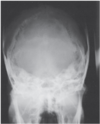

In Figure A, which of the localization lines is used for the lateral projection of the skull?

A - Line 1

B - Line 2

C - Line 3

D - Line 4

A

The lateral projection of the skull requires that the patient be in the prone oblique position with the MSP parallel to the IR and the interpupillary line perpendicular to the IR. The IOML (line 3) must be parallel to the long axis of the IR and perpendicular to the front edge of the IR. The supraorbital margins, anterior clinoid processes, and posterior clinoid processes should be superimposed.